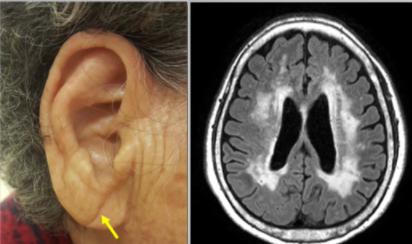

| 2) 귓볼 주름 확인하기 |

귓볼에 주름은 뇌의 노화와 관계가 깊다.

거울을 보시고 귓볼에 주름이 있는지 확인해보시기 바랍니다.

귓볼에 주름은 뇌의 노화와 관계가 깊다고 합니다.

귓볼에 주름이 생기는 원인은 귀의 각 부위 특히 귓볼부위의 미세혈관까지 혈액순환이 원활하지 않음을 보여준다고 합니다. 이와 연관하여 뇌의 작은 혈관들에 혈액순환이 원활하지 않아 막히게 되며 위의 우측 MRI사진의 뇌 중앙부가 하얗게 변성되는 경우가 있다고 합니다.

100% 일치하는 것은 아니지만

귓볼에 혈액순환이 잘 안된다. → 뇌 안의 작은 혈관도 혈액순환이 안될 수 있다.

이렇게 이해하시면 될듯합니다.

귓볼 뿐만아니라 몸 구석구석 뇌 안의 미세한 혈관까지 혈액순환을 시킬 수 있도록 많은 노력을 기울여야 합니다.

※ 귓볼 주름이 심하고, 운동기능 저하 및 기억력이 줄어드는 게 느껴지는 경우 꼭 정밀검사받아보시기 바랍니다.